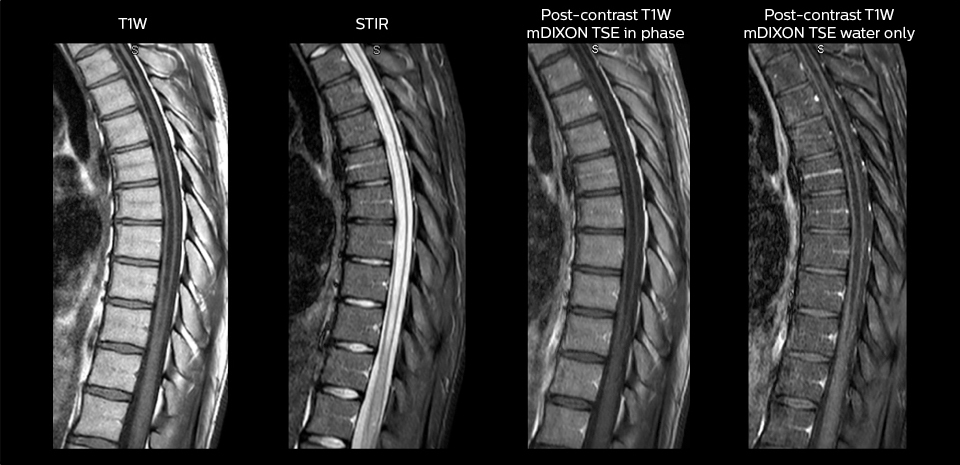

“We use mDIXON TSE extensively in our spine imaging in the emergency room,” says Dr. Karis. “It’s particularly nice in that it is very robust with regard to susceptibility type of problems that would come up with traditional spectral fat-saturated images; these problems are essentially eliminated with the mDIXON technique. In our ED environment it’s really nice to have the fat-free imaging that goes along with the mDIXON technique.

“For the thoracic and cervical spine routine non-contrast exam, for example, we perform one mDIXON T2 TSE sequence, which provides us with two outputs: the fat-and-water-together T2-weighted images, as well as the water-only sagittal T2-weighted images. And then we also perform an axial gradient echo exam.”

To minimize the time taken to perform scans, rapid MRI examination protocols (ExamCards) were developed, shortening the total scanning time to even less than 10 minutes in some exams. Techniques like mDIXON (modified DIXON) are used for robust capturing of fat-free MRI images in a hectic ED environment.